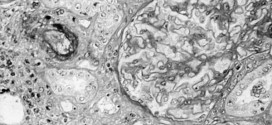

La arteritis obliterante. Dureza y engrosamiento anormales de las paredes arteriales, resultado de inflamaciones, especialmente de la túnica íntima con tendencia a la obliteración del vaso. Por: Salvador Gregori, binipatia.com Resumiendo: También llamada arteritis obliterante de los miembros inferiores (o AOMI), es una enfermedad que resulta de la disminución del calibre de las arterias que suministran sangre a las extremidades inferiores. …

La hepatitis C (VHC), es la inflamación del hígado, por causa vírica. Resumiendo: Causada por el virus análogo a los flavivirus, con un genoma de ARN de más de 9000 nucleótidos (parecido a los virus del dengue y de la fiebre amarilla); cierta heterogeneidad genética. La infección de hepatitis C es causada por el virus de la hepatitis C (VHC). …

El lupus eritematoso sistémico (LES). También con otros nombres parecidos o similares como: lupus, lupus eritematoso discoide, lupus vulgar, lupus crónico discoide, lupus pernio, lupus TBC, lupus neonatal, lupus agudo o sistémico, lupus eritematoso verrugoso, lupus eritematoso hipertrófico, lupus profundo (paniculitis), etc. Resumiendo: Enfermedad desconocida a saber. La cual los tejidos y células pueden ser dañados por el depósito de …